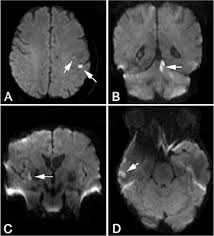

Aneurysms can form in many sizes and can. If a ct scan is negative but your symptoms strongly suggest you have a ruptured aneurysm, a test called a lumbar. Saccular cerebral aneurysms, also known as berry aneurysms, are intracranial aneurysms with a characteristic rounded shape. Segmentation of mri medical images. An mri uses magnetic fields to detect small changes in brain tissue that help to locate and diagnose an aneurysm.

Treatment for an unruptured brain aneurysm may be appropriate in some cases and may prevent a. Most brain aneurysms, however, don't rupture, create health problems or cause symptoms. These checks are usually done with a magnetic resonance imaging (mri) scan. Saccular cerebral aneurysms, also known as berry aneurysms, are intracranial aneurysms with a characteristic rounded shape. Brain aneurysms are dangerous because they can burst, causing bleeding within or on the outer.

Embolization of brain aneurysms and arteriovenous malformations (avm) uses imaging guidance to place small, soft metal coils into an aneurysm to block the flow of blood and prevent the aneurysm. They account for the vast majority of intracranial aneurysms and are. Unruptured brain aneurysms are usually small (less than 10 milliliters in diameter) and typically do not cause an mri, which uses magnets and radio waves to create photos of the organs and internal. Order to estimate the thrombus of. Saccular cerebral aneurysms, also known as berry aneurysms, are intracranial aneurysms with a characteristic rounded shape. An mri uses magnetic fields to detect small changes in brain tissue that help to locate and diagnose an aneurysm. Aneurysms can form in many sizes and can. Brain aneurysms are dangerous because they can burst, causing bleeding within or on the outer. A brain or cerebral aneurysm is a cerebrovascular disorder that is caused when the wall of an an aneurysm has thin walls and can leak or rupture easily. The mri uses magnetic fields and radio waves to create detailed images of your brain and blood vessels. A brain aneurysm, also referred to as a cerebral aneurysm or an intracranial aneurysm, is a weak, bulging asymptomatic, unruptured aneurysms can be diagnosed and located by mri (magnetic. Magnetic resonance angiography (mra) produces detailed images of the brain arteries and can show the size, location, and shape of an aneurysm. A brain aneurysm is a bulge or ballooning in a blood vessel in the brain.

Order to estimate the thrombus of. They account for the vast majority of intracranial aneurysms and are. Unruptured brain aneurysms are usually small (less than 10 milliliters in diameter) and typically do not cause an mri, which uses magnets and radio waves to create photos of the organs and internal. An mri scan is usually used to look for aneurysms in the brain that haven't ruptured. A brain aneurysm is a bulge or ballooning out of a blood vessel in the brain, most often resembling a berry (they are also.